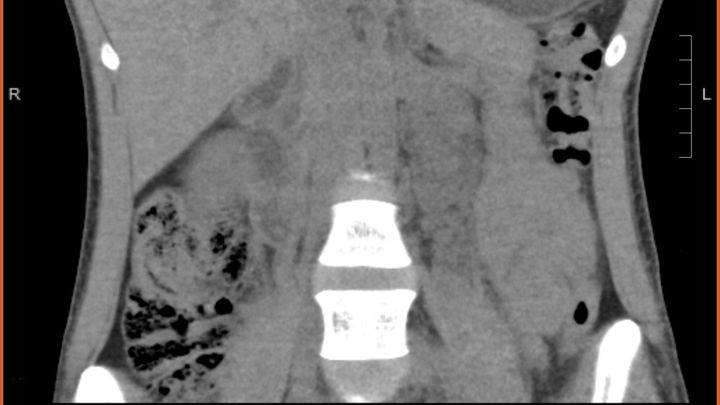

Aloha to all my friends & family. This has been something I have been trying to avoid for a long time; as most people know, I’m not one to ask for help unless there’s no other option. I have been diagnosed with a neurogenic tumor the size of a grapefruit, in my abdomen that has been taking a detrimental toll on my body and health. My tumor was discovered on Memorial Day weekend after multiple trips to the emergency room. Since then, I have gone through multiple rounds of testing and biopsies to diagnose the issue. We are still on the path of diagnosis as there are many different types of neurogenic tumors, but I have faith that we will find all the answers. I will be getting exploratory surgery on December 6th followed by chemotherapy and multiple de-bulking surgeries in the near future. My surgeon and procedures are all in San Francisco, which has required my parents & partner to miss out on work to help me with travel. I am hoping to help relieve the financial strain on us all through this time. I was raised by the strongest family imaginable, I know all will be well in due time. I also want to thank all my aunties, uncles, and cousins that have been so supportive since the beginning. Truly so blessed to be surrounded by so much love and I am so grateful for it all!